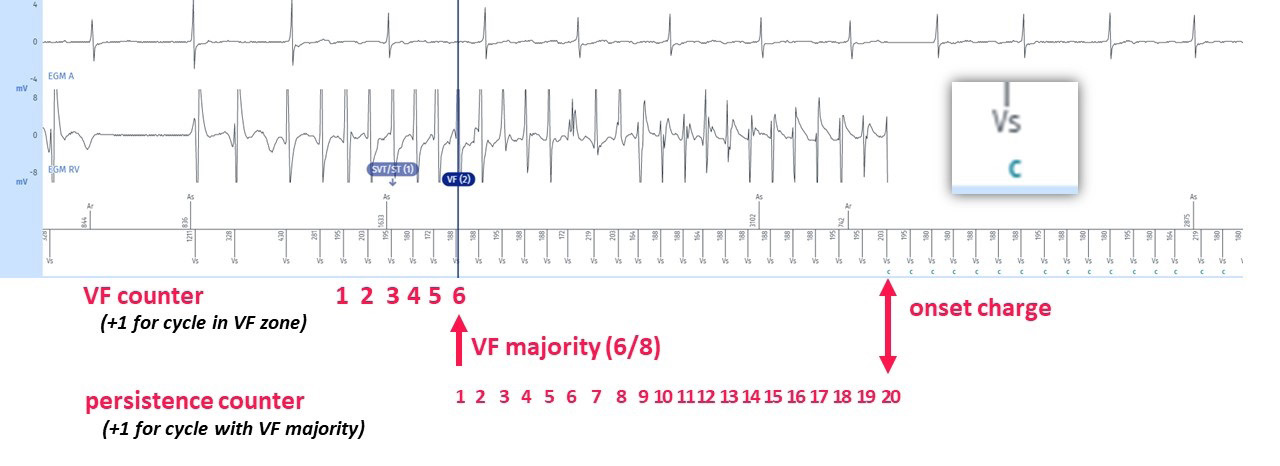

Tracings: The tracing at the top entitled EGM A is the atrial electrogram, the tracing underneath entitled EGM RV is the ventricular electrogram, lastly, at the bottom, the atrial markers above the line and ventricular markers below, along with the time intervals. The gain can be changed at the top (now set at X 2). The running speed can also be changed, ranging from 12.5 to 100 mm/sec.

The EGM shows the following elements

1 An intrinsic rhythm with spontaneous atroventricular conduction rhythm at baseline;

2 A few ventricular extrasystoles which seem to be associated with the onset of a polymorphic tachycardia above 220/min, perfectly detected, with a slow and regular atrial rhythm, and small amplitude signals on the atrial channel which are far-field signals of ventricular origin and not detected by the atrial chain;

3 After 6 out of 8 cycles in the VT zone, the diagnosis of SVT/ST is made (marker 1); this is often seen in VF episodes and is caused by the “warming” up of many ventricular arrythmias. The combination of fast cycles (PVCs and the onset of VF) and slow cycles (compensatory pauses or differences in cycles often seen during “warming up” period) results in the VT criteria being fullfilled before the VF criteria. As the rythm is unstable, it is considered SVT by the discrimination algorithm, therefore we see a first marker

SVT/ST, rather than VT of VF.

4 After a majority of 6 out of 8 cycles in the VF zone, the diagnosis of VF is made shown by the marker VF (2). It should be pointed out, even before the course on discrimination, that the discrimination criteria (PARAD+) are not active because it is the VF zone.

5 After diagnosis of VF, treatments are not directly delivered as we want to give the tachycardia the chance to self-terminate. The tachycardia needs to complete the persistence counter before therapies are delivered. After 20 persistence cycles, as programmed (and as recommended), during which the diagnosis of VF is confirmed at each cycle, according to the 6/8 majority, the capacitor charges (« C »). Indeed, no burst was triggered because the rate is above the 220 – 255/min zone. (If the tachycardia

had been within this aforementioned zone, and if it had been stable, then a burst would have been triggered. If the tachycardia had been within this zone but conversely unstable, then an immediate shock would have been delivered without a prior burst).

The EGMs show normal functioning of the defibrillator. The counting of the events is carried out as follows:

1 Each ventricular cycle detected outside refractory periods is classified as: Slow, VT or VF, depending on the programming of the tachycardia zones.

2 In a sliding window of 8 cycles and for each cycle, the device classifies RR cycles with a 16-ms margin in a histogram. Paced cycles do not enter into the constitution of the histogram.

3 In the present case, 75% of the 8 cycles, hence 6, must be in the VF zone for the diagnosis to be established. For a therapy to be triggered, it is necessary that the persistence of the programmed number of cycles is fulfilled (in this instance 20 cycles, according to the recommendations), with the VF majority detected for each cycle. The last 4 cycles determine the initiation of therapy due to FVT or VF: each of the last 4 cycles are analysed and if any of the latter is in the VF zone above the FVT zone, the

assigned therapy will be a 42 J shock (depending on the programming), and the charge of the capacitors begins.

4 All tachycardia cycles are in the VF zone during the charge which is therefore continuous. It is on the ensuing cycle which follows the end of the charge and which is in VF zone that the shock is delivered.